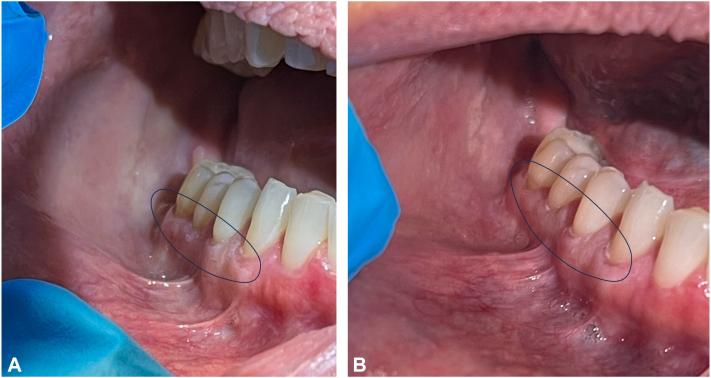

Treatment of oral lichen planus using deucravacitinib.

https://cdn.ncbi.nlm.nih.gov/pmc/blobs/cffa/10861938/b4991ed6a36e/gr1.jpg